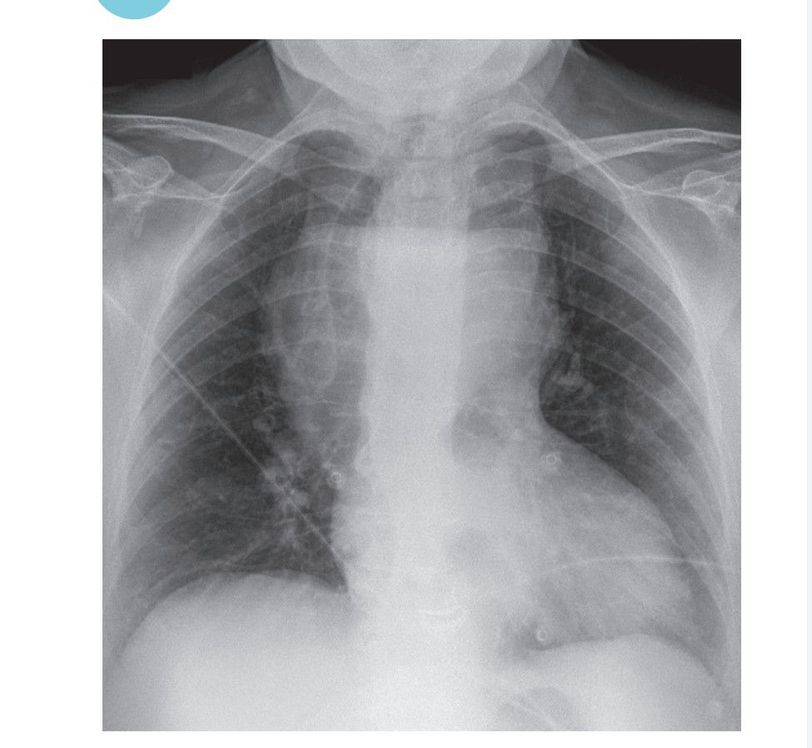

Diagnosis???

Thymoma?

Lymphoma